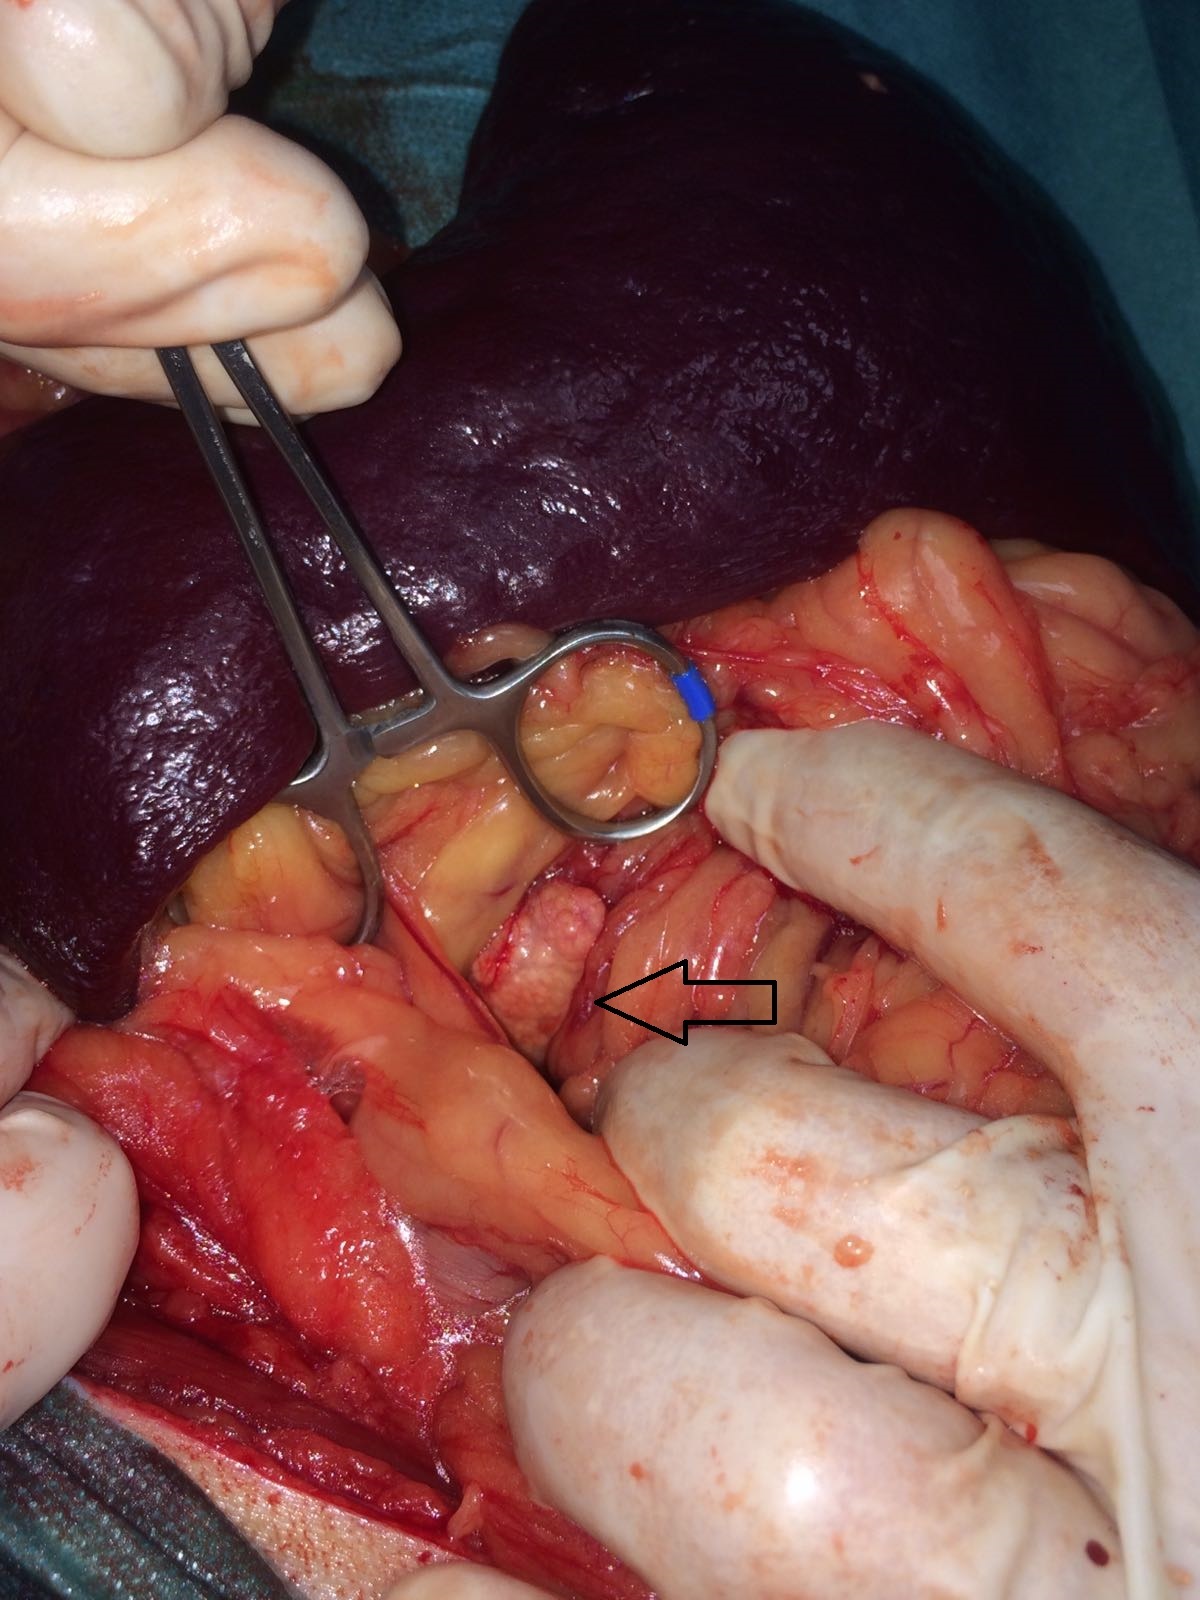

Für Chicko waren nun Blut- und Urintests in unserer Praxis und auch im externen Labor gemacht worden, Röntgen, Ultraschall und unzählige klinische Untersuchungen hatte der Rüde mitgemacht, und nichts hatte die Ursache für sein Gallenleiden hervorbringen können. Wir zogen die letzte Konsequenz: Eine Probe-Laparotomie sollte gemacht werden, eine operative Eröffnung seines Bauches, um zu sehen und zu fühlen, was der Galle auf der Strecke von der Gallenblase zum Darm den Weg versperrte, und um gegebenenfalls Proben von Leber und Galle zu nehmen.

Eine Narkose an einem leberkranken Hund plant man nicht leichtfertig, da fast alle Narkose- und Schmerzmittel einen negativen Effekt auf die Leber haben. In der OP zeigte sich aber, dass die Entscheidung für den Eingriff richtig gewesen ist. Die Bauchspeicheldrüse schien vergrößert - möglicherweise ein Tumor. Das Rätsel nach dem Grund der Stauung der Galle war damit gelöst.